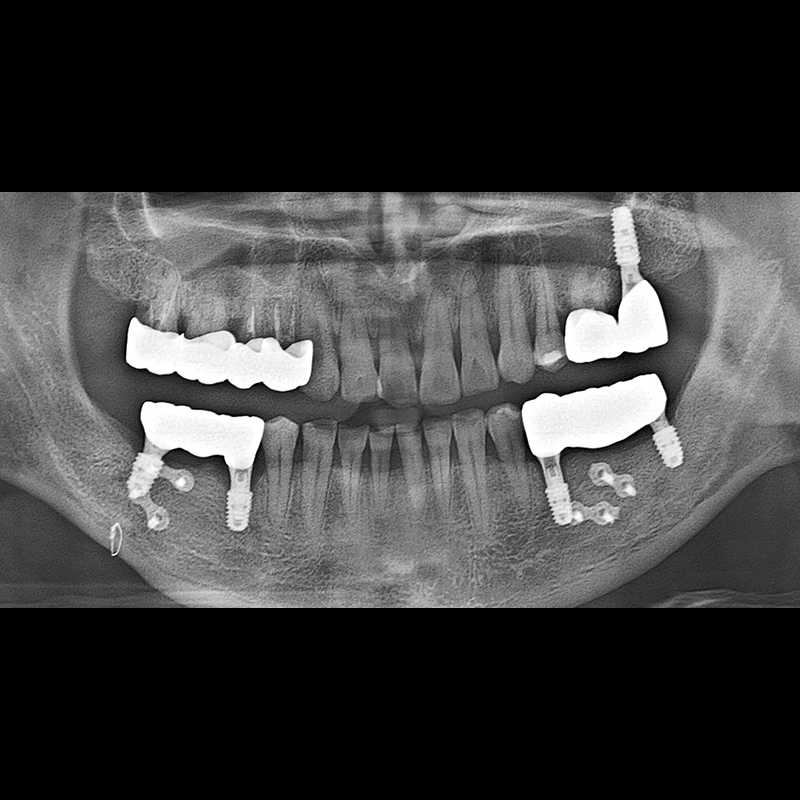

BEFORE AFTER

Implant before and after 2025.05.30

Implants were placed in the missing tooth and in the tooth position where it was difficult to save.